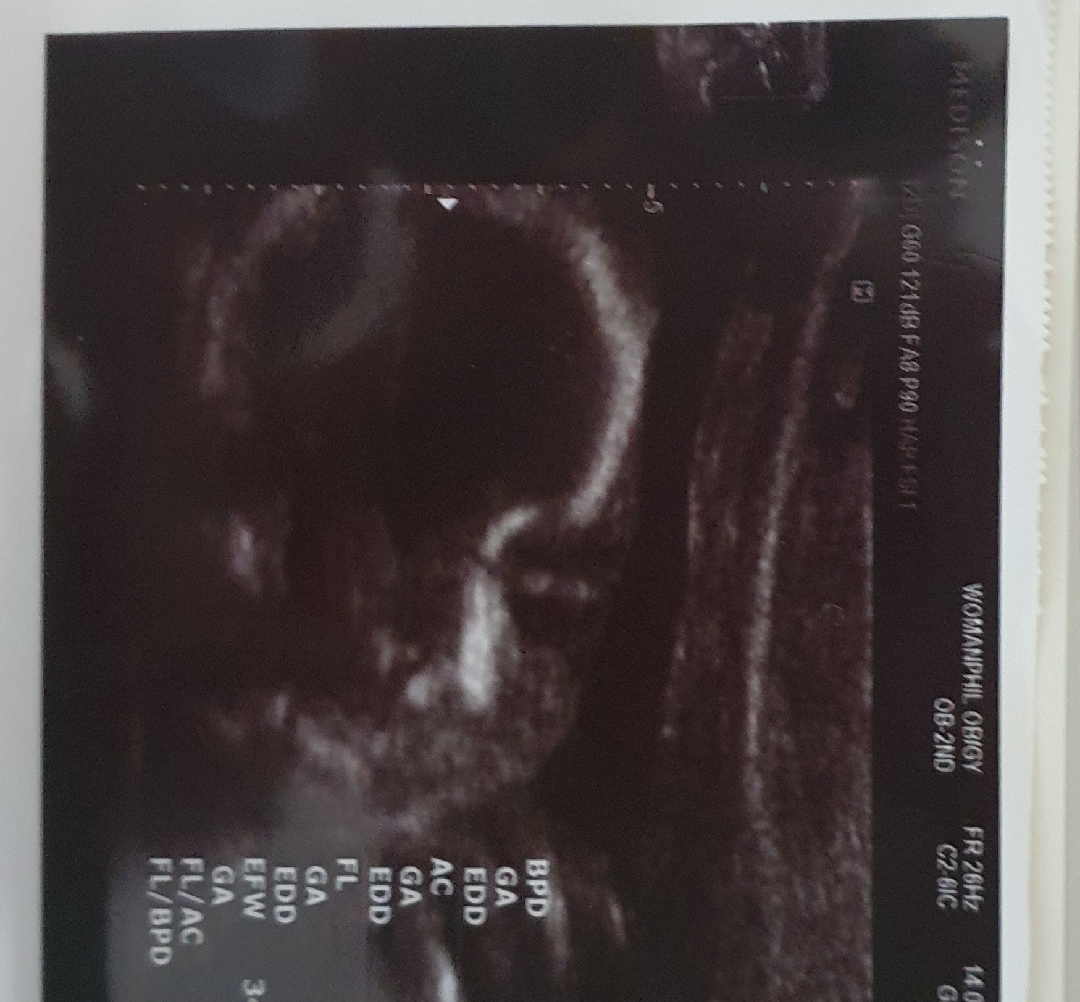

우리애기눈뜬건가요?ㅋ

눈뜨고잇는건가요? 21주인데 벌써 눈뜨나용?ㅋ

ㅋ감사해여~~ ㅋ 눈을뜬건지 뭔지ㅋㅋ

어머낫! 그런거같네요 진짜😲 신기해요!ㅋㅋㅋ

그쵸?ㅋㅋ 저도 볼때마다 희한하네~생각해요ㅋ